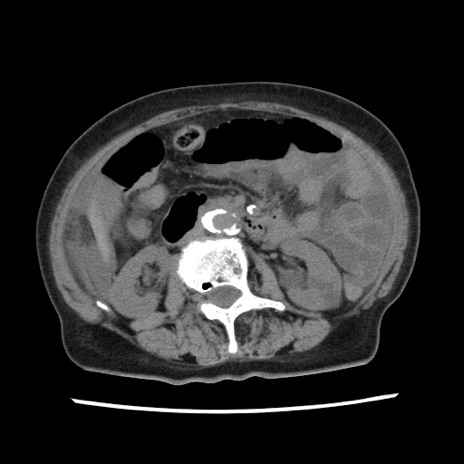

症例1(横断像)

【症例】80歳代女性

【主訴】腹痛

【現病歴】8時間前から腹痛あり来院。

【既往歴】糖尿病、脂質異常症、子宮体癌にて子宮全摘術

【身体所見】意識清明・会話良好だが腹痛で苦悶様、全腹部にわたって反跳痛と圧痛あり

【データ】WBC 13600、CRP 0.14、LDH 224、CK 90